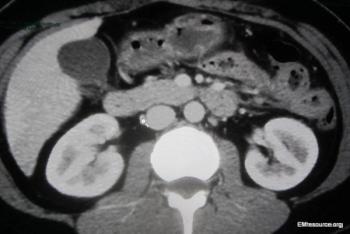

The patient has had 10 episodes of bleeding in the past 24 hours. Can you find clues to the underlying problem in the history and on the CT scan?